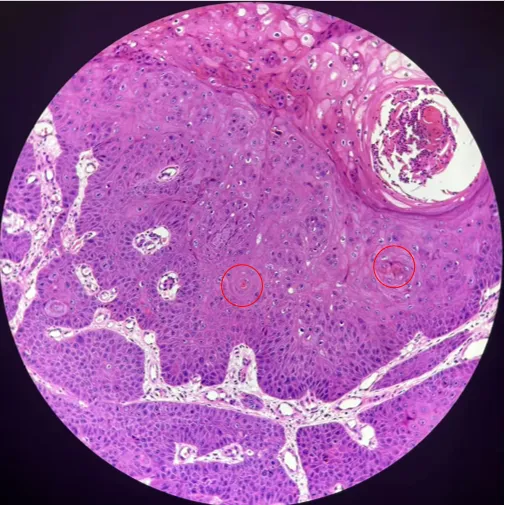

组织病理:

肿瘤由异型增生的鳞状上皮细胞构成,细胞大小不一、多形性明显;细胞核大、深染、核质比增高,核仁显著,可见病理性核分裂象

浸润型鳞状细胞癌